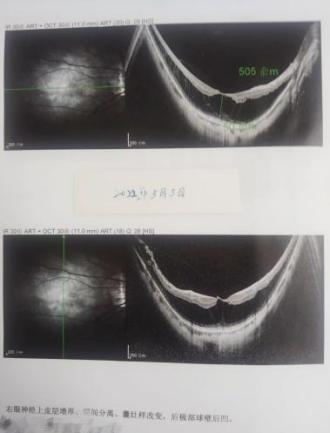

于2025年11月5日在外院行右眼黄斑区多发裂孔视网膜脱离复位手术;11月12日林女士在家人陪伴慕名来到厦门眼科中心分院泉州华厦眼科医院找眼底病学科带头人李勇院长看诊,经过检查OCT显示右眼黄斑区两个裂孔不全闭合(下图3):

( 图3 Oct检查报告)